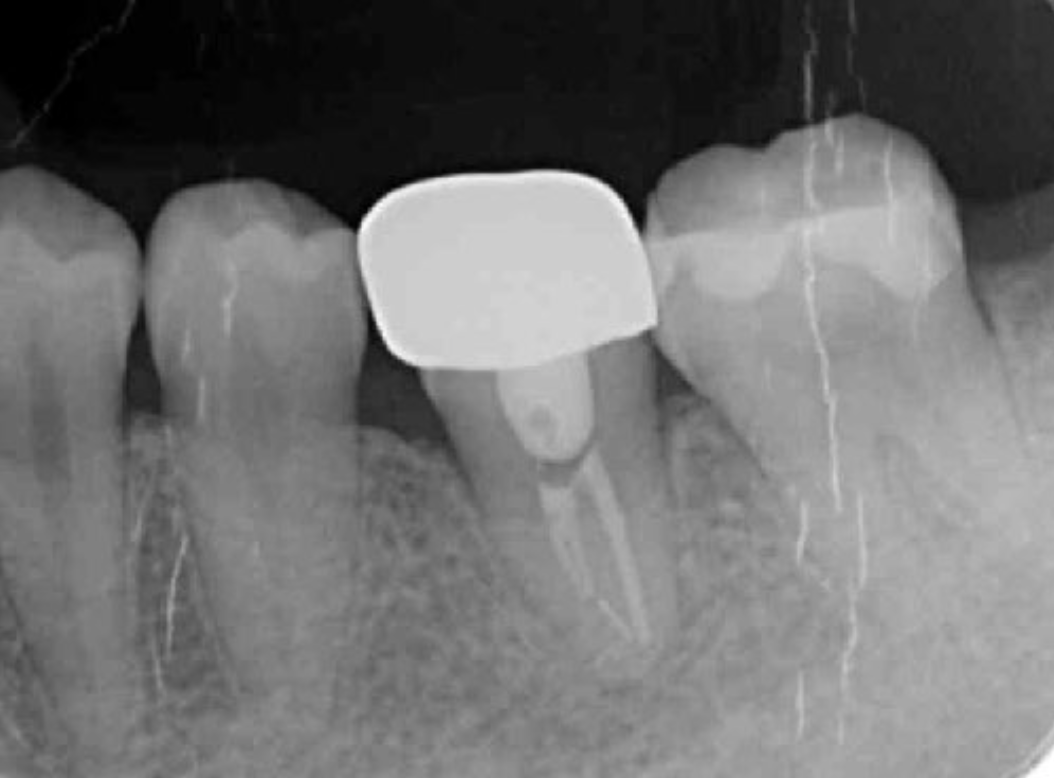

Figure 11.Dental X-ray image obtained after autotransplantation from #38 to #36. The donor tooth root canal appeared to be blanched.